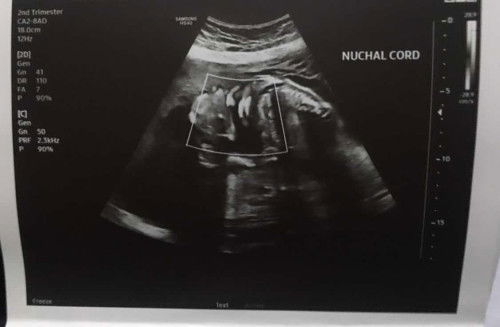

BREECH and Umbilical Chord

hi mommies meron ba sa inyo na may experience na 5 months or 22 weeks tapos breech si baby and may umbilical chord na naka patong or nakapalupot sa leeg niya (not sure pa kasi if naka patong lang or napalupot sa leeg niya yung umbilical chord. pa help naman po. pa share ng experiences niyo… di ko kasi sure if papa hilot ako or kung antayin ko lang pumosition si baby medyo nakakatakot po kasi